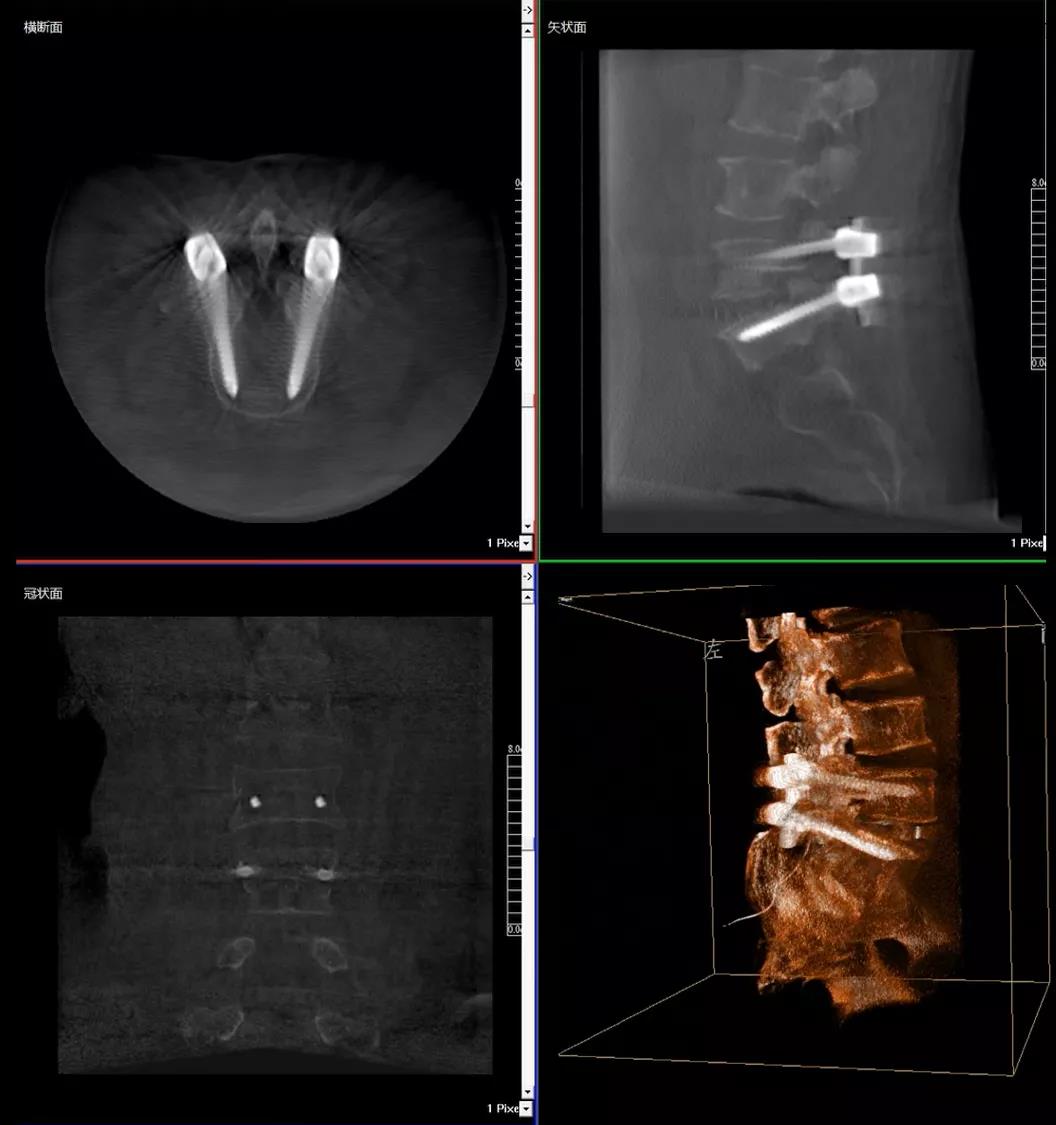

患者1:女性,56歲,L5/S1椎間盤椎板減壓+釘棒固定術

患者下腰部疼痛,活動受限,伴有左下肢疼痛5年,久站或彎腰干活時疼痛加劇,臥床休息后疼痛癥狀緩解,近一個月情況加重,需行椎板減壓+釘棒固定術。

醫生在影像引導下在L5/S1椎弓根處打入醫用螺釘

術中快速生成橫斷面、矢狀面、冠狀面斷層圖像和三維立體圖像